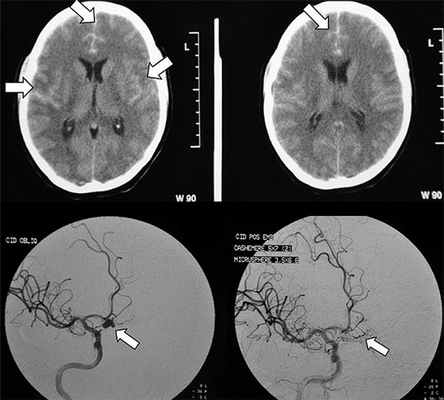

Субарахноидальное кровоизлияние (САК) - кровоизлияние в подоболочечное пространство головного мозга, которое проявляется, как правило, общемозговой симптоматикой (чрезвычайно интенсивной головной болью, рвотой, утратой сознания) и менингеальным симптомокомплексом. Подтверждается диагноз при проведении люмбальной пункции и компьютерной томографии (КТ) головного мозга. У лиц, злоупотребляющих алкоголем, существуют сложности в диагностике САК. С одной стороны, у них отмечается стертость клинической симптоматики, с другой – есть соблазн «списать» все имеющиеся симптомы на проявление алкоголизма. Так, в неврологический стационар нередко поступают больные после длительной алкоголизации с серией эпиприпадков. После того, как пациенты приходят в сознание, часть из них предъявляют жалобы на умеренной интенсивности головную боль (но не такую острую, как у лиц без алкоголизации), у других – она вовсе отсутствует (или же в связи с эмоциональными расстройствами, снижением критики они ее отрицают, затрудняются описать). В неврологическом статусе определяются симптомы, соответствующие синдрому энцефалопатии, либо энцефалополинейропатии. Менингеальные знаки отсутствуют или выражены крайне скудно. Люмбальная пункция выявляет кровянистый ликвор, после центрифугирования обнаруживается ксантохромия - единственно достоверный признак, отличающий кровь, полученную при кровоизлиянии, от путевой. При проведении нейровизуализации определяются характерные для субарахноидального кровоизлияния изменения на КТ головного мозга. Трудности диагностики возникают при несвоевременном использовании параклинических методов обследования - слишком ранней люмбальной пункции (достоверные изменения в ликворе появляются через 12 часов), или поздней (через 2-3 недели), когда кровь не определяется ни в ликворе, ни на КТ (максимально надежны показатели КТ в первые сутки, они выявляют САК у 95% больных, в последующие дни надежность метода падает, и к концу первой недели составляет лишь 50%).

Таким образом, необходима определенная настороженность при обследовании лиц, злоупотребляющих алкоголем, в связи со стертостью клинической симптоматики САК (отсутствия или незначительной выраженности головной боли, рвоты, менингеальных знаков), недооценкой всего спектра клинических проявлений САК - комы, судорожных припадков, делирия (неверная их интерпретация как проявления токсической энцефалопатии). Возможно постепенное развитие симптоматики, присоединение менингеальных знаков на 2 - 3 сутки, что требует динамического наблюдения. Своевременное проведение параклинических методов исследования - люмбальной пункции (наиболее достоверны результаты от 12 часов до 2 суток с момента кровоизлияния), КТ головного мозга (в первые часы после заболевания) помогут избежать диагностических ошибок у данной категории больных.

- Компьютерная томография помогает определить стадию САК, его выраженность и выявить наличие крови в желудочках мозга или веществе мозга.